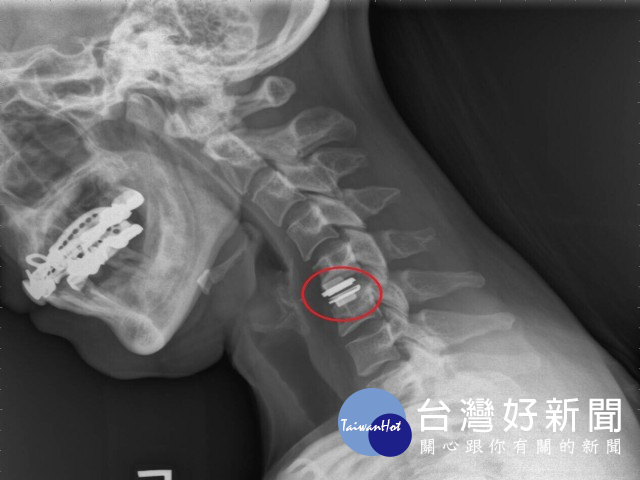

62歲榮民頸椎病變,長年頸部疼痛及手麻痛感,最期症狀加劇,手無力、無法躺平。經大甲李綜合醫院院長暨神經外科權威醫師張迪生檢查後,確認頸椎病變,建議進行「頸椎人工椎間盤置換」,施以「微創腰椎手術」,隔天即可自由活動,亦不需戴頸圈,讓老榮民終於能睡得一好覺。

醫師張迪生表示,腰椎退化是老年人常見的病症之一,微創與傳統腰椎手術的目的,都是為了減輕神經的壓迫與椎體穩定和關節面平衡,此兩種手術在文獻研究與臨床下,其神經減壓與骨融合的術後結果是相同的,差別在於使用的手術方法不同。傳統的脊椎手術傷口較大,容易造成手術部位的正常結構組織傷害,術後恢復期長,且容易產生後遺症。

相反的,「微創腰椎手術」的安全性相對增高,因為傷口小手術創傷低,故手術出血量也會偏少,且不需切開肌肉,可盡量保留肌肉功能,減少對背部肌肉和軟組織的傷害,一般傷口在一公分左右,術後疼痛感比起開放性手術少了許多,病患術後恢復良好,隔日即可下床行走及出院,與傳統手術相比其術後產生之後遺症較少。

大甲李綜合醫院張迪生院長強調,多數人年老後因關節中的軟骨退化,而出現「骨刺」症狀,在不影響生活作息的情況下,是不需開刀的,除非麻痛感覺加劇並造成生活不便,且病症符合手術條件,以現今手術而言微創手術是較安全的,不同於傳統觀念認為開「龍骨」是很傷身的事,建議有相關症狀之患者,手術前需充分與主治醫師溝通討論後,並依醫師的臨床評估為依據,視疾病種類選擇最合適的手術方式,是非常重要的。